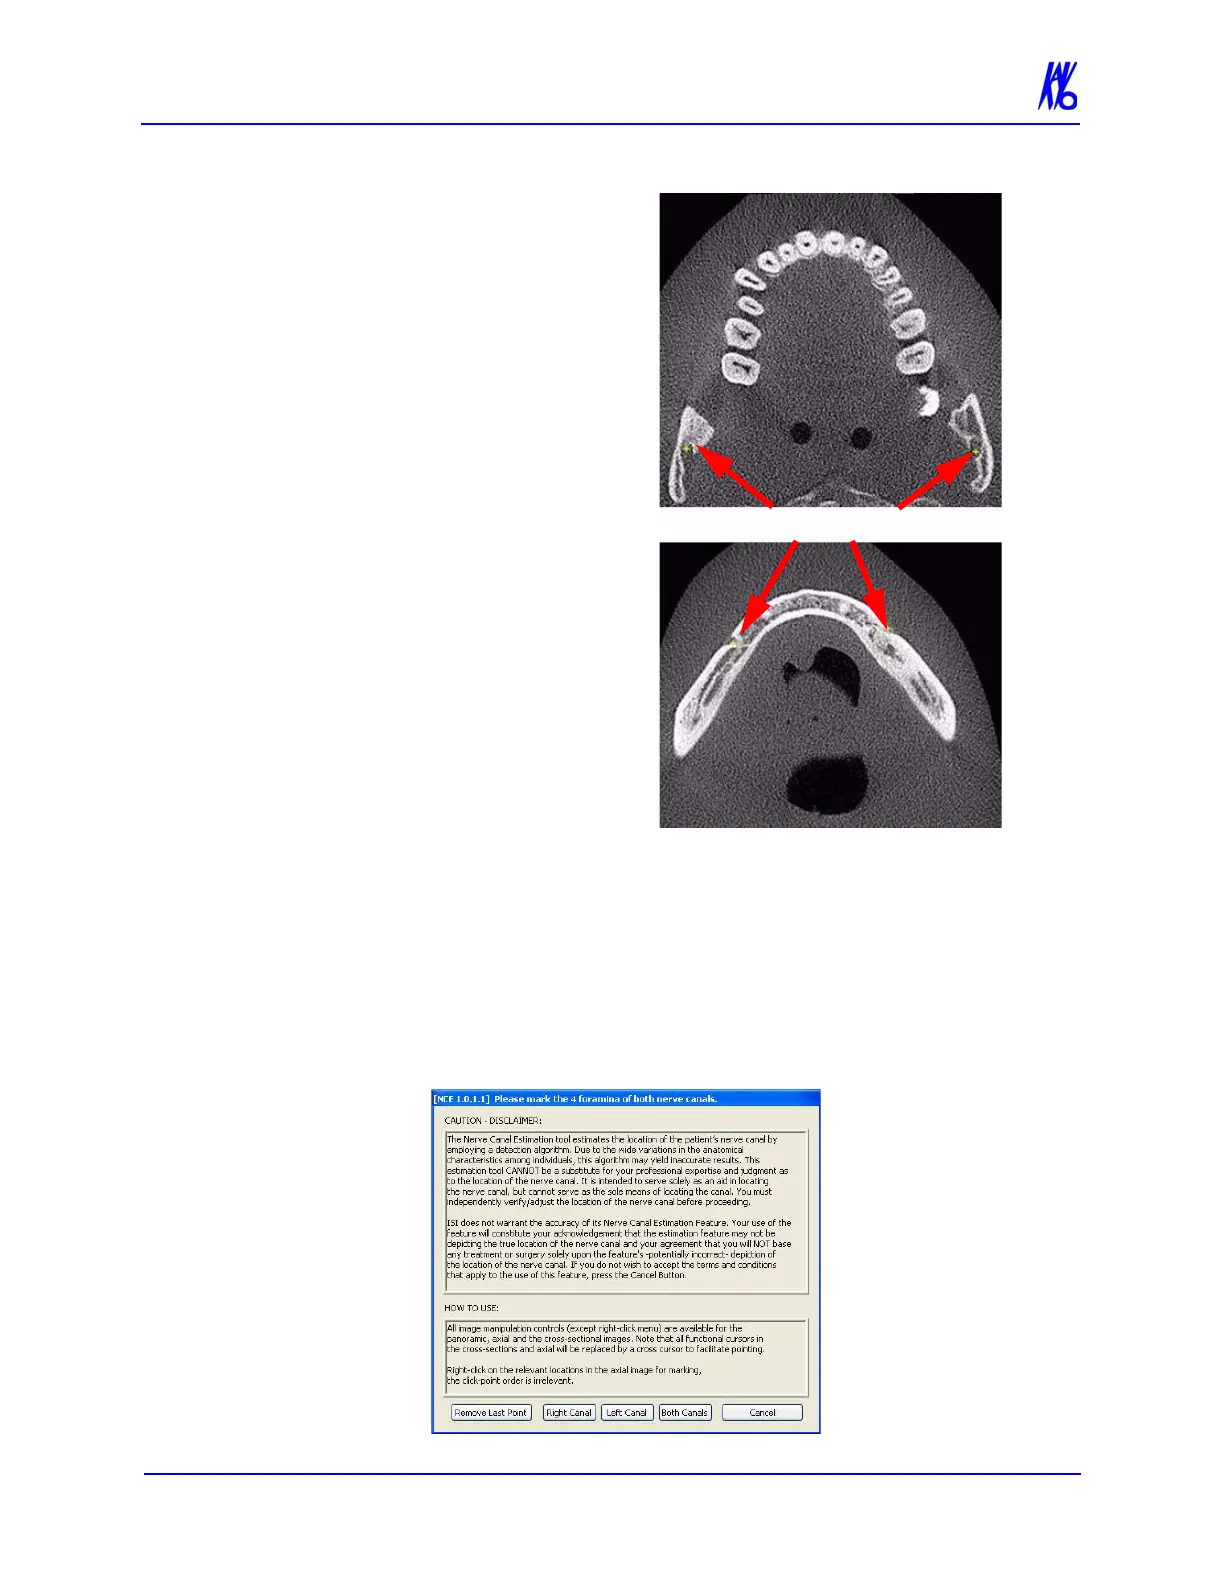

2. Manipulate the axial view

to locate the anterior left

and right nerve canals.

3. Right-click to mark the

relevant points on the

axial view. The click and

point order is irrelevant.

A cross is displayed

marking each point

selected on both the axial

and panoramic map view.

5. Repeat steps 2 through 4

to mark the posterior left

6. When all points are selected for right, left or both canals, one or

all of the following buttons are displayed. Click desired button

to confirm the marking of the selected nerve canal(s). The canals

are calculated and displayed on the panoramic map view.